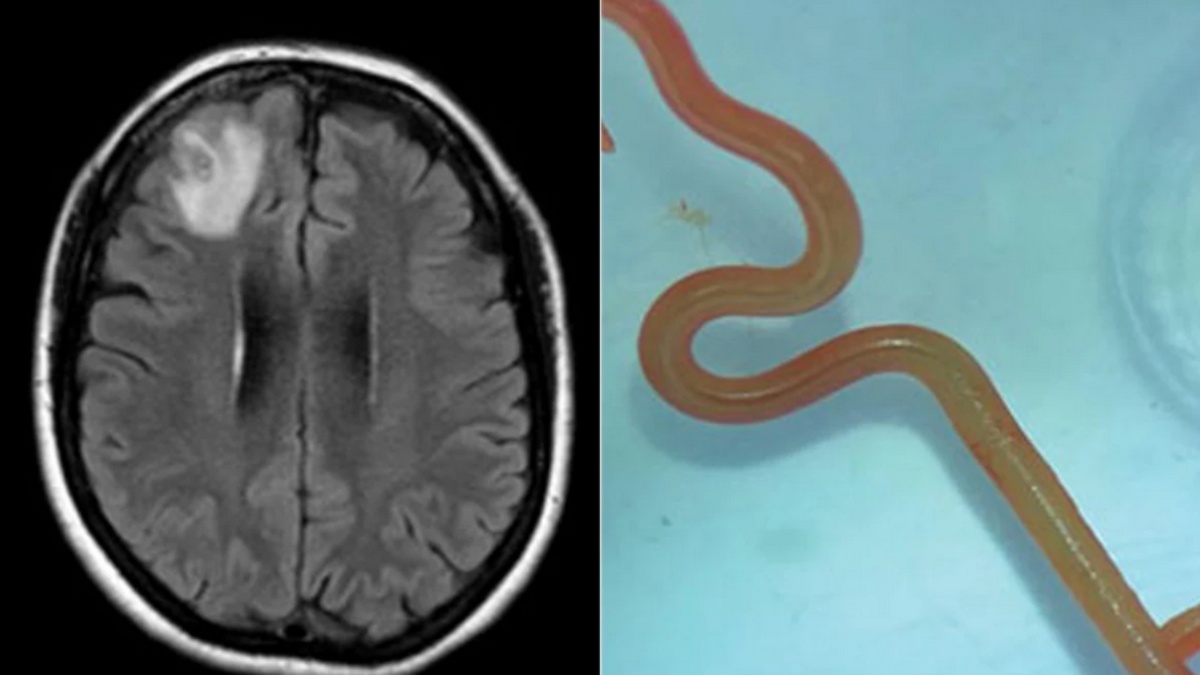

ஆஸ்திரேலியாவில் நியாபக மறதி மற்றும் மன அழுத்த பிரச்சினையால் அவதிப்பட்ட பெண் ஒருவர் மருத்துவமனைக்கு சென்றுள்ளார். அவருக்கு பல்வேறு பரிசோதனைகளை செய்த போதும் என்ன பிரச்சினை என மருத்துவர்களால் கண்டறிய முடியவில்லை. இதையடுத்து தலைப்பகுதியில் எம்.ஆர்.ஐ ஸ்கேன் செய்து பார்த்த போது, மூளைக்குள் 8 செ.மீட்டர் நீளத்தில் உயிருடன் ஒரு ஒட்டுண்ணி புழு இருந்தது கண்டறியபட்டுள்ளது.

இதனால், தலைநகர் கான்பெராவில் உள்ள மருத்துவமனையில் அந்த பெண் அனுமதிக்கப்பட்டார். மருத்துவர்கள் எம்.ஆர்.ஐ ஸ்கேன் செய்து பார்த்த போது மூளையில் வினோதமாக எதோ இருப்பது தெரியவந்தது. இதனால் அறுவை சிகிச்சை செய்ய வேண்டிய தேவை ஏற்பட்டுள்ளது. இது பற்றி மருத்துவர்கள் கூறுகையில், மூளையில் ஏற்படும் தொற்று பாதிப்புகளுக்கு அவ்வப்போது நரம்பியல் நிபுணர்கள் சிகிச்சை அளிப்பது வழக்கம்.

ஆனால் இதுபோன்று மூளையில் ஒட்டுண்ணி புழு இருந்தது இதுவரை யாரும் அறிந்திடாதது. பெண்ணின் மூளையில் இருந்தது ஓபிடாஸ்காரிஸ் ராபர்ட்ஸி என்ற இனத்தை சேர்ந்த லார்வா புழுவாகும். மருத்துவ வரலாற்றிலேயே இது ஒரு யுனிக் விஷயமாக பார்க்கப்படுகிறது" என்றார். ஆஸ்திரேலிய பெண்ணுக்கு ஏற்பட்ட இந்த பாதிப்பு பற்றிய தகவல் Emerging Infectious Diseases என்ற இதழில் பதிவு செய்யப்பட்ட்டுள்ளது.